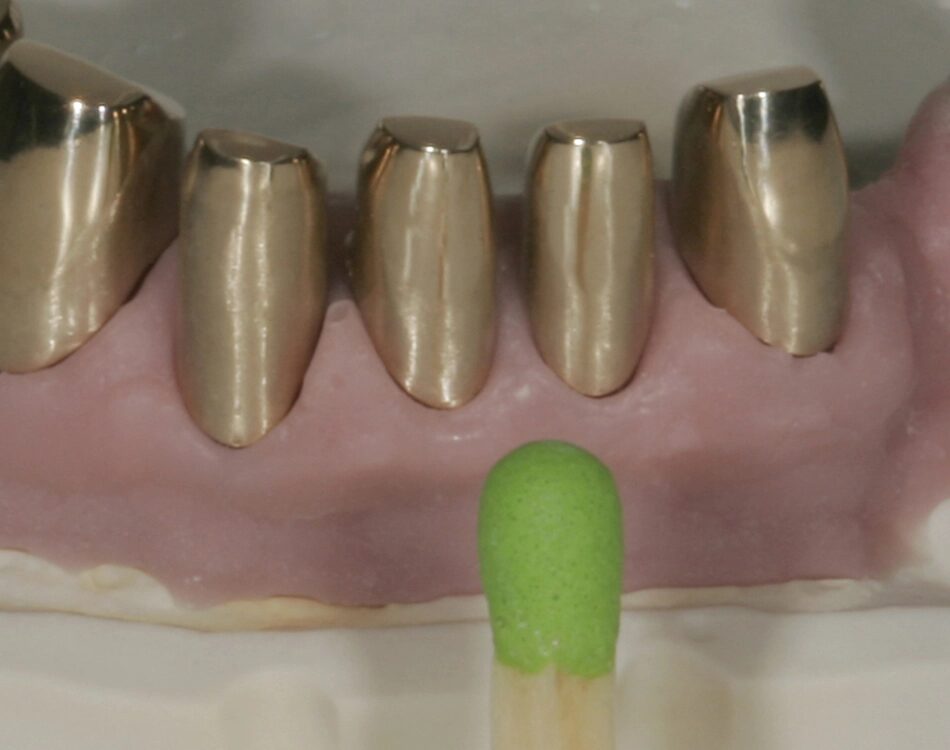

Schrittweise wird okklusal mittels Polierwalzen bis zum Hochglanz verfeinert. Die eigentlichen Fräsflächen belassen wir jedoch immer seidenmatt. Unserer Erfahrung nach verändert jegliche Politur die Flächen unkontrollierbar. Die fertigen Primärteile (Abb. 32) bestechen durch den wertigen Farbton und die perfekte Oberfläche. Nicht erkennbar sind die minimalen Stärken- und Größenverhältnisse. Erst im Vergleich mit einem handelsüblichen Standardstreichholz wird die Schwierigkeit offensichtlich (Abb. 33): Hier wurde mit Materialstärken von 0,2 mm, punktuell sogar noch weniger gearbeitet.